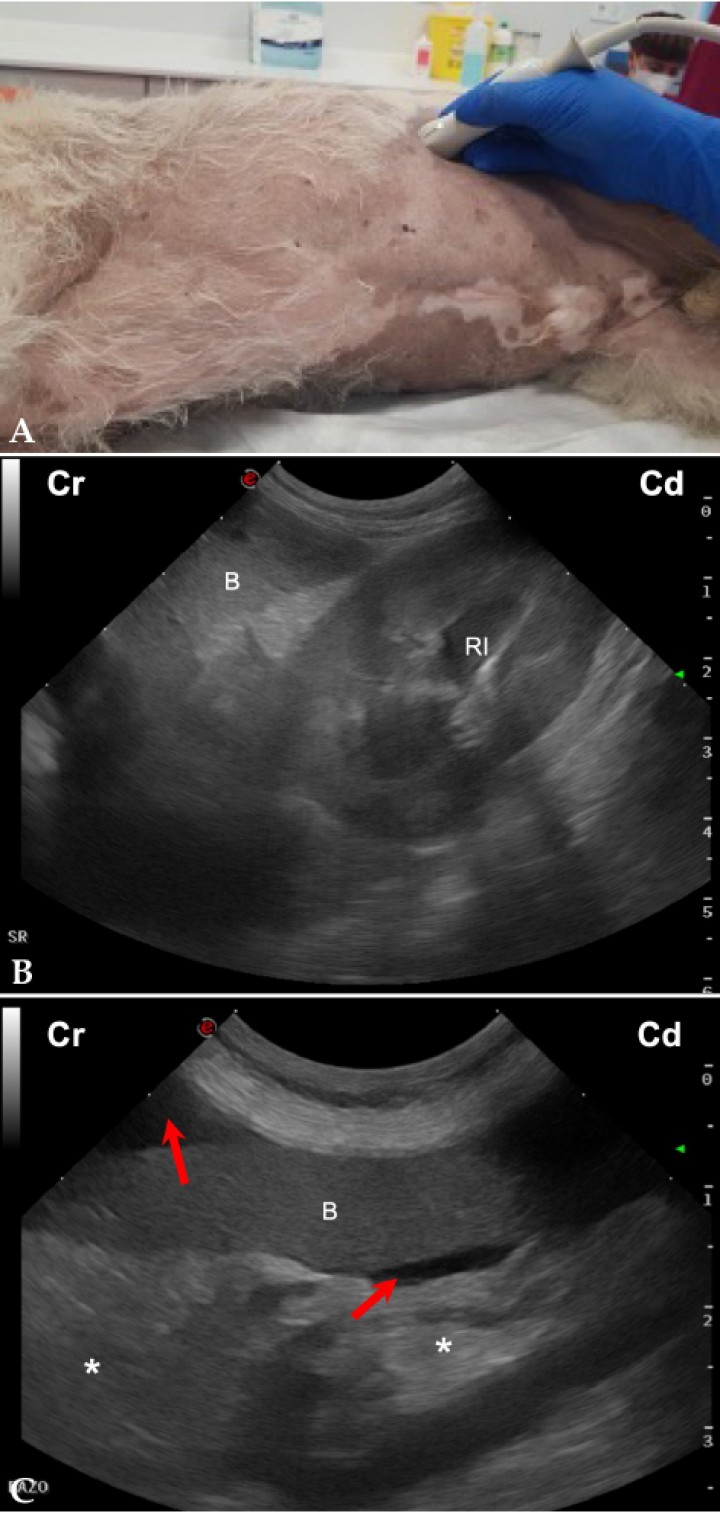

- Vista del flanco izquierdo (Fig. 2A): Permite una evaluación del área esplenorrenal (SR) y de la zona entre la pared abdominal y el bazo (Figs. 2B y 2C).[ Boysen SR, Lisciandro GR: The Use of ultrasound for dogs and cats in the emergency room. AFAST and TFAST. Vet Clin Small Anim 2013; 43: 773-797. [PubMed] , Lisciandro GR: The abdominal FAST (AFAST) exam. En Lisciandro GR (ed): Focused ultrasound techniques for the small animal practitioner, Oxford, Wiley Blackwell, 2014; 17-43. , Kinns J: Abdomen. En Barr F, Gaschen L (ed): BSAVA Manual of canine and feline ultrasonography, Gloucester, BSAVA, 2011; 72-84. ]

<p>(<strong>A</strong>) Posicionamiento de la sonda de ecografía para obtener la vista del flanco izquierdo. (<strong>B</strong>) Imagen ecográfica del área esplenorrenal (SR) de un perro sano, en la que se observa el bazo (B) y el riñón izquierdo (RI) en corte longitudinal. Cr: craneal; Cd: caudal. (<strong>C</strong>) Imagen ecográfica del área esplenorrenal (SR) de un perro con hemoabdomen, en la que se observa líquido libre anecogénico (flechas rojas) alrededor del bazo (B) y la grasa peritoneal ligeramente hiperecogénica (asteriscos). Cr: craneal; Cd: caudal.</p>

Figura 2

(A) Posicionamiento de la sonda de ecografía para obtener la vista del flanco izquierdo. (B) Imagen ecográfica del área esplenorrenal (SR) de un perro sano, en la que se observa el bazo (B) y el riñón izquierdo (RI) en corte longitudinal. Cr: craneal; Cd: caudal. (C) Imagen ecográfica del área esplenorrenal (SR) de un perro con hemoabdomen, en la que se observa líquido libre anecogénico (flechas rojas) alrededor del bazo (B) y la grasa peritoneal ligeramente hiperecogénica (asteriscos). Cr: craneal; Cd: caudal.